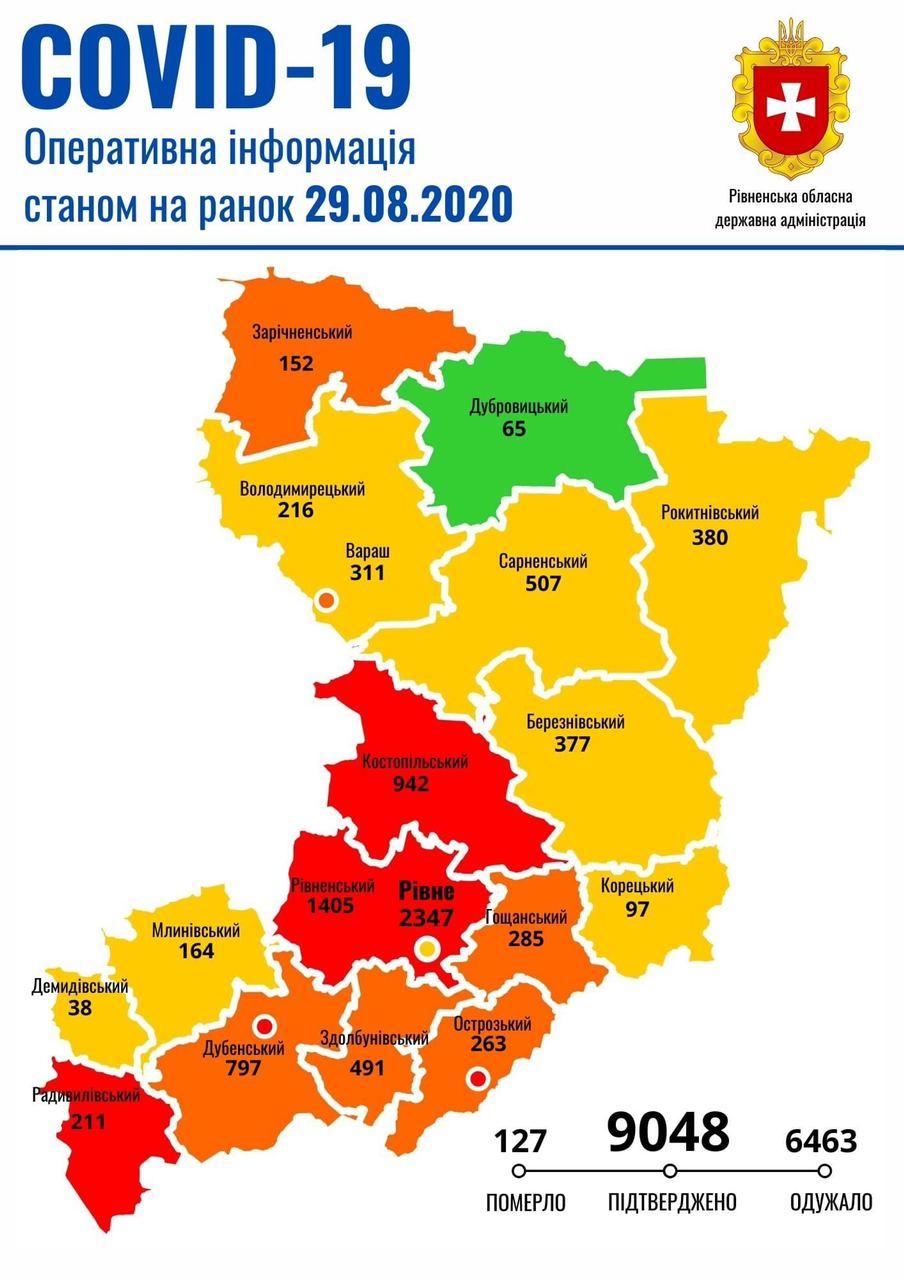

Коронавірус повертається: як стрімко зростає кількість хворих на Рівненщині (ВІДЕО)

Пів тисячі - у важкому стані, 9 жителів Рівненщини померли за добу від коронавірусу

Більше 3 тисяч випадків захворювання на коронавірус зафіксували в Україні за добу

COVID-19 на Рівненщині: 32 нових випадки, серед них 4 дітей, ще одна людина померла